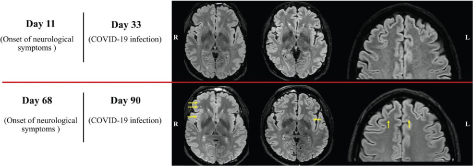

Fig 1

Figure 1. The trend in neuroradiological detection of white matter changes in our patient is summarised. FLAIR images from the second (top row) and the third (bottom row) MRI examinations. Several new subcortical white matter changes were found and are highlighted with yellow arrows. The discrepancy was not considered to be explained by the slight difference in image quality. All other sequences in all three MR examinations showed normal findings.

The first two MRI scans (day 2 and day 11 from neurological symptom onset) were negative (Figure 1, top row). When we compare the first DTI analysis (day 11) with the HC group, the right uncinate fasciculus (UF) and the cortico-spinal tract (CST) displayed focal signs of myelin changes compared with HC (high fractional anisotropy [FA], low axial diffusivity [AD] and low radial diffusivity [RD]). The right frontal aslant tract (FAT) and the right inferior fronto-occipital fasciculus (IFOF) displayed signs of axonal changes (low FA, low AD and low RD, highlighted in red in Figure 2). The other analysed white matter bundles did not show a significant difference compared with HC. In the third scan (day 68), several new, rounded subcortical white matter changes had appeared in frontal and sub-insular regions (predominantly in the right hemisphere) (Figure 1, bottom row). When the second DTI analysis (day 68) was compared with the first one and the HC group, we identified a partial regress of myelin changes in the right UF, the right CST and in the right IFOF. The right FAT showed steady focal axonal changes between investigations (at the compared AD abnormalities distribution), while the left horizontal component of the superior longitudinal fasciculus (hSLF) displayed new significant diffusion changes possibly reflecting myelin damage (low FA, high AD and high RD).